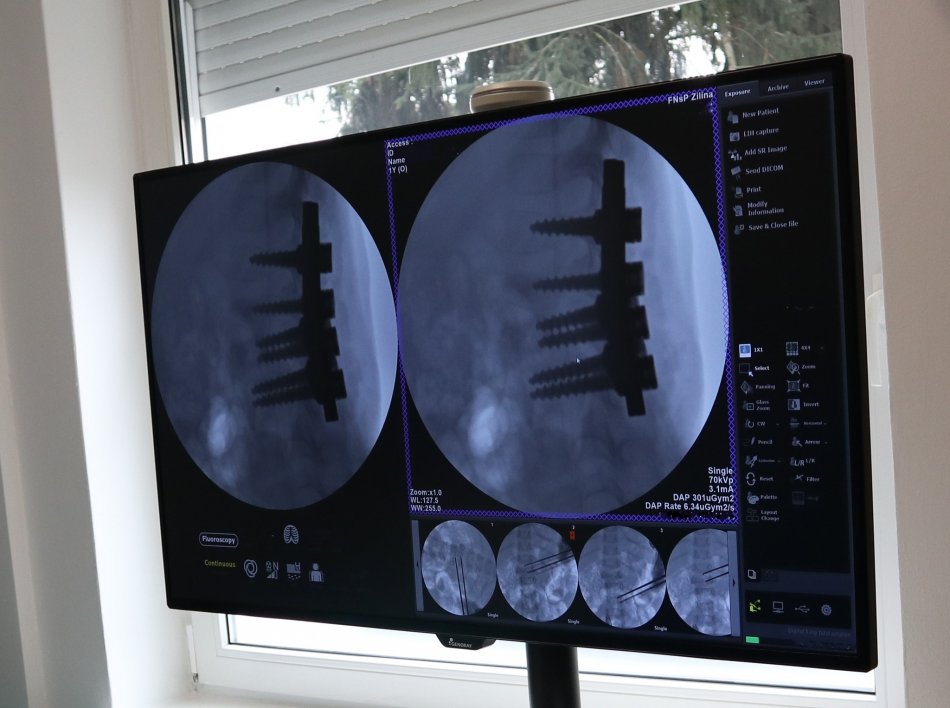

Galéria k článku Úžasný ÚSPECH slovenských lekárov! Keby 2,5-ročné dieťa neoperovali, mohlo by OCHRNÚŤ

Zdroj: FNsP Žilina